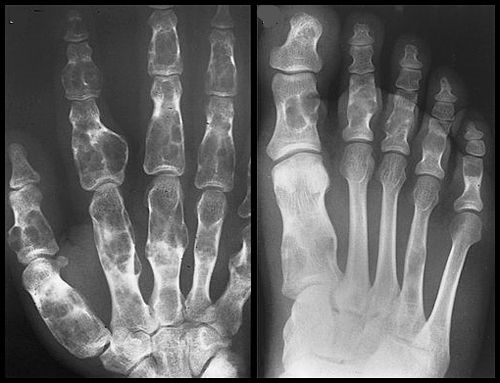

Síndrome de Maffucci

El síndrome de Maffucci es un trastorno congénito no hereditario, caracterizado por encondromatosis y angiomatosis de los tejidos blandos: viscerales o mucocutaneos. La hemangiomatosis puede situarse en la piel y en el tejido subcutáneo. Los hemangiomas son generalmente cavernosos y pueden ser unilaterales o bilaterales, localizados o extensos. Las lesiones esqueléticas en el síndrome de Maffucci tienen la misma distribución que en la enfermedad de Ollier, especialmente en los huesos de las manos y los pies.

Su nombre se debe al patólogo italiano Angelo Maffucci, quien lo describió en el año 1881. En este síndrome los encondromas son más frecuentes en los huesos cortos de las manos y pies y son diagnosticados durante la edad preescolar. El diagnóstico diferencial de estas dos entidades es difícil, debido a sus similitudes, por lo que se ha propuesto que son diferentes grados de expresión de una misma patología. El origen de estas enfermedades aún es desconocido, pero se cree que se debe a una displasia mesodérmica congénita o a una anomalía cromosómica aún no identificada.

Las radiografías de la en condromatosis de las manos y los pies son características. Se ven masas radiolucentes de cartílago con focos de calcificación, parecidos a los de los encondromas solitarios, que deforman severamente los huesos. Los encondromas en esta localización pueden ser intracorticales y periosteales. Algunas veces sobresalen de la diáfisis de los huesos cortos o largos, y asemejan a los osteocondromas. Pero estas proporciones nunca poseen una cubierta cartilaginosa de un tallo óseo. En los huesos largos se ven bandas radiolucentes que se extienden desde el platillo decrecimiento hasta la diáfisis. La coalescencia de encondromas metafisarios, a menudo provoca un agrandamiento asimétrico de los huesos largos.

En el síndrome de Maffucci radiográficamente se observan múltiples flebolitos calcificados junto con las típicas alteraciones de la encondromatosis.